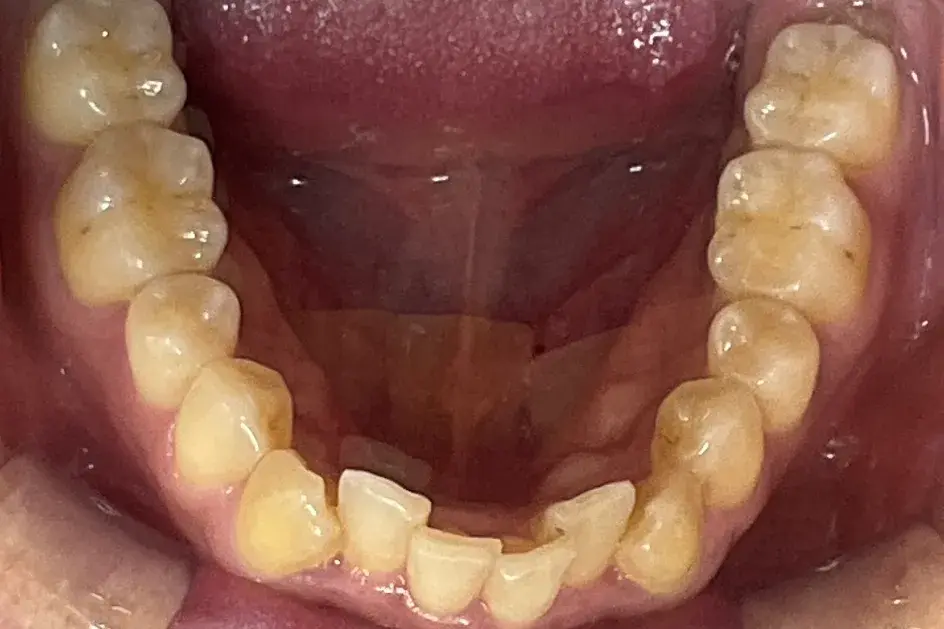

- 症例2

治療期間 4カ月

治療費 23.1万円(月額1,925円~)

※上顎前歯部、下顎前歯部の叢生をマウスピース型矯正装置で改善したケース。矯正治療上のリスクとして、治療中の虫歯、歯根吸収、歯肉炎 ・歯周炎の発生などが考えられる。